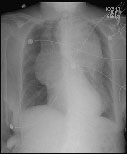

A frontal radiograph of the chest demonstrating a very dilated, air filled esophagus in a patient with achalasia.